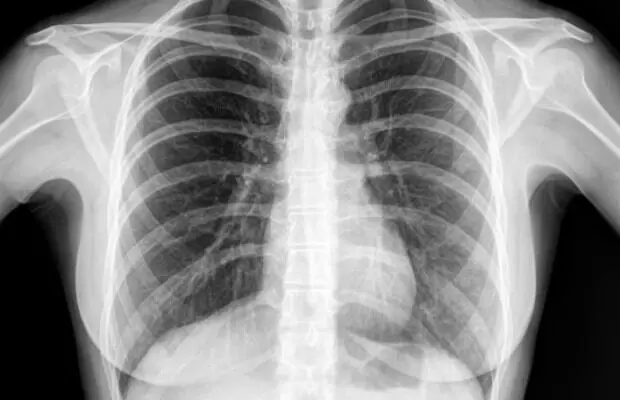

Getting a Chest X-Ray: చెస్ట్ ఎక్స్ రే తీయించుకుంటున్నారా? ఈ విషయం తెలుసుకోండి

Getting a Chest X-Ray: తరచుగా ఛాతి ఎక్స్రేలు (Chest X-rays) తీయించుకోవడం వల్ల అనవసరమైన రేడియేషన్ ప్రభావం పెరిగే అవకాశం ఉంటుంది. దీనిని డాక్టర్లు, రేడియాలజిస్టులు జస్టిఫికేషన్ ,ఆప్టిమైజేషన్ సూత్రాల ఆధారంగా మాత్రమే చేస్తారు.సాధారణంగా ఒకే ఒక్క ఛాతి ఎక్స్రే ద్వారా వచ్చే రేడియేషన్ చాలా తక్కువగా ఉంటుంది. ఇది దాదాపు 10 రోజులలో సహజ వాతావరణం నుండి మనకు లభించే సహజ నేపథ్య రేడియేషన్ కంటే కొంచెం ఎక్కువగా మాత్రమే ఉంటుంది.

మీకు నిజంగా అవసరమని డాక్టర్ భావించినప్పుడు మాత్రమే ఎక్స్రే తీసుకోవాలి.ఆధునిక డిజిటల్ ఎక్స్రే యంత్రాలు చాలా తక్కువ రేడియేషన్ డోస్ను ఉపయోగిస్తాయి, ఇది ప్రమాదాన్ని మరింత తగ్గిస్తుంది. డాక్టర్ సలహా మేరకు తీసుకునే ఒక్క ఛాతి ఎక్స్రే వల్ల ఎటువంటి ప్రమాదం లేదు. కానీ, తరచుగా అనవసరంగా తీసుకుంటే, కాలక్రమేణా మొత్తం రేడియేషన్ మోతాదు పెరిగి, సిద్ధాంతపరంగా దీర్ఘకాలిక ఆరోగ్య ప్రమాదం పెరిగే అవకాశం ఉంటుంది.